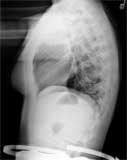

Lateral chest on a normal female.